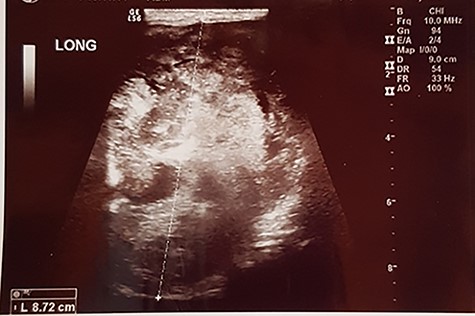

A 57-year old male presented to surgery outpatient clinic of the hospital with scrotal mass. His initial review of systems was negative for any complaints except a feeling of heaviness at the scrotum. On clinical examination, the mass was mobile and did not transilluminate. The lesion had gradually increased in size during the last 2 years. The overlying skin was normal. The patient’s medical history like his family was normal. Ultrasound revealed a weak and heterogeneous echogenic mass (Fig. 1), and after the imaging with computed tomography (CT) and magnetic resonance imaging (MRI) (Figs 2 and 3) of the pelvis, we proposed surgical excision of the mass. Preoperatively, there was no suspicion of the diagnosis of aggressive angiomyxoma. Moreover, the differential diagnosis was between lipoma and testicular malignances. We preferred a perineal procedure with patient in lithotomy position; also the team was composed of a general surgeon and an urologist. We extracted a mucoid mass en bloc with free macroscopic margins. The mass was 11 cm in its max diameter, this was extended to the pubic symphysis and displaced the urethra without infiltrated it. The histological examination revealed small spindle-shaped cells without atypia or mitosis proliferating in an edematous to fibrous stroma and numerous small- to medium-sized thick-walled vessels. Around the mass was a smooth muscle integument. The neoplasmatic cells had the expression of desmin, CD34, S100, vimentin, smooth muscle antibody, estrogen receptor 40%, progesteron receptor 20% and Ki67-5%. Postoperatively, our patient had an uneventful recovery. A postoperative SPECT was negative for metastatic disease, and the 2-year follow-up is negative for recurrence of the disease.

Aggressive angiomyxoma is a rare entity most frequently between reproductive age women (male/female: 1/7) [3]. Aggressive angiomyxoma or deep angiomyxoma as referred by the world health organization is a mesenchymal malignancy first described in 1983 by Steeper and Rosai. This tumor most commonly derived from the female vulvar region, pelvis and perineum and male scrotum and inguinal region, but there are a few cases with non-pelvic invasion [4, 5]. At the most cases, angiomyxoma is an asymptomatic gradually enlargement mass, the symptoms in most patients are swelling without pain, abdominal distention, hematuria or vaginal hemorrhage in women. In our case, the only symptom was the palpable mass of the scrotum [1, 6]. The differential diagnosis of the palpable mass of scrotum in men patients is between perineal cyst, inguinal hernia, hydrocele, lipoma, abscess, leiomyoma, leiomyosarcoma, liposarcoma, testicular tumors or unidentified masses. The examination of the mass should begin with ultrasound tomography, which demonstrates a hypoechoic, well-demarcated mass with multiple thin echogenic internal septa, and for more detailed imaging, we can use computed tomography or magnetic resonance imaging, which on T2 weighted image has high signal intensities, or digital subtraction angiography to recognize the details of mass structure, to identify the relations between the near anatomical structures in order to organize the operation. Aggressive angiomyxoma has a distinctive imaging appearance of swirled or layered pattern in the tumor after enhancement on CT and MRI [7–9] with intravenous contrast injection. Preoperative diagnoses require high degree of suspicion. There are a few cases with preoperative histological diagnoses with CT assisted biopsy, but in most described cases the diagnosis was made postoperatively with the histological examination of the mass. Histologically, the typical findings include stellate to spindle-shaped tumor cells with fibromyxoid stroma and hyalinized thin-to-thick wall vessels and no necrosis or cystic changes, and the immunohistochemical studies show the expression of vimentin, smooth-muscle actin and CD34 to be strongly positive, the desmin, estrogen receptors and progestin receptors to be median positive, but mostly negative for S-100 and CD68 [3]. The more effective treatment for aggressive angiomyxoma is the radical free margin surgical excision. However, the risk of local recurrence is high especially within 2–3 years after the first operation. A reason for local recurrence is the incomplete surgical excision; however; Chan et al. [6] report no difference in recurrence in patients with negative margins compared with those with positive margins. In general, aggressive angiomyxoma has no tendency for distal metastases, but there was a report of a case with lung and mediastinum metastases. Radiation therapy has proposed as a monotherapy or as control of multiple recurrences after surgical excision, with poor results [10]. Chemotherapy has poor results in aggressive angiomyxoma because of the slow progress of the disease. Monotherapy may has a role in control of these tumors because of the expression of ER and PR receptors.